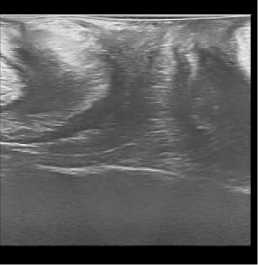

По результатам проведенных контрольных УЗ исследований нами было установлено, что при трансректальном исследовании толщина ректовагинальной перегородки увеличилась в среднем с 1,1+/–0,2 см до 1,5+/–0,2 см. Перегородка со стороны прямой кишки обрела четкие контуры за счет уменьшения ее складчатости. Произошло уменьшение диастаза бульбокавернозных мышц с 0,9+/–0,2 см до 0,3+/–0,1 см. При трансперинеальном УЗИ уменьшилась толщина перегородки за счет снижения ее складчатости и регрессировал пролапс перегородки в сторону влагалища при натуживании пациенток (рис. 1).

До операции

После операции

До операции После операции

Рис. 1. УЗИ картина до и после операции

Fig. 1. Ultrasound picture before and after surgery